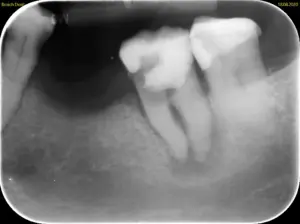

Toter Zahn mit Knochenauflösung um die Wurzel, tiefe Karies bis in den Wurzelbereich, vor einer bereits bestehenden Zahnlücke. Hier macht der Aufwand zum Zahnerhalt des Problemzahns wohl keinen Sinn.

Die Summe der Probleme fällt das Urteil.